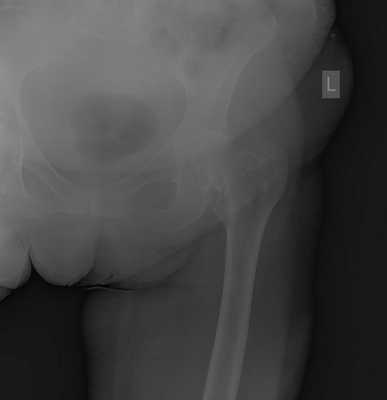

Пациентка Ж, 28 лет. Обратилась в К+31 в октябре 2017. Страдала врождённым подвывихом головки правого бедра, лечение в детсве не проводилось (на тот момент рутинного УЗИ скрининга в СССР не было, а к детскому ортопеду направляли не всех детей). В возрасте 23 лет отметила появление болей в области правого тазобедренного сустава. На протяжении последних 3 лет отмечала нарастание болевого синдрома, нарушение походки, ограничение амплитуды движений и постепенное укорочение конечности. Обратилась в К+31, выполнены рентгенограммы на которых визуализируется коксартроз 3 ст справа на фоне дисплазии правого тазобедренного сустава.

Принято решение о выполнении тотального эндопротезирование правого тазобедренного сустава протезом бесцементной фиксации пара трения керамика-керамика, с восстановлением длины конечности.

Снимки после операции. Длина конечности восстановлена. В сравнении со снимками до операции хорошо видно как восстановилось нормальное положение тазового кольца и поясничного отдела позвоночника. Пациентка была прооперирована в день поступления, переведена из РАО через 2 часа после операции, активизирована через 6 часов после операции. На вторые сутки обучена ходьбе с дополнительной опорой на костыли.